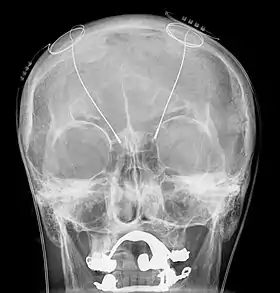

- 3 May – In the United Kingdom's first successful ocular implant trial, two men blinded by retinitis pigmentosa have their sight partially restored by prototype microchip implants.[77]